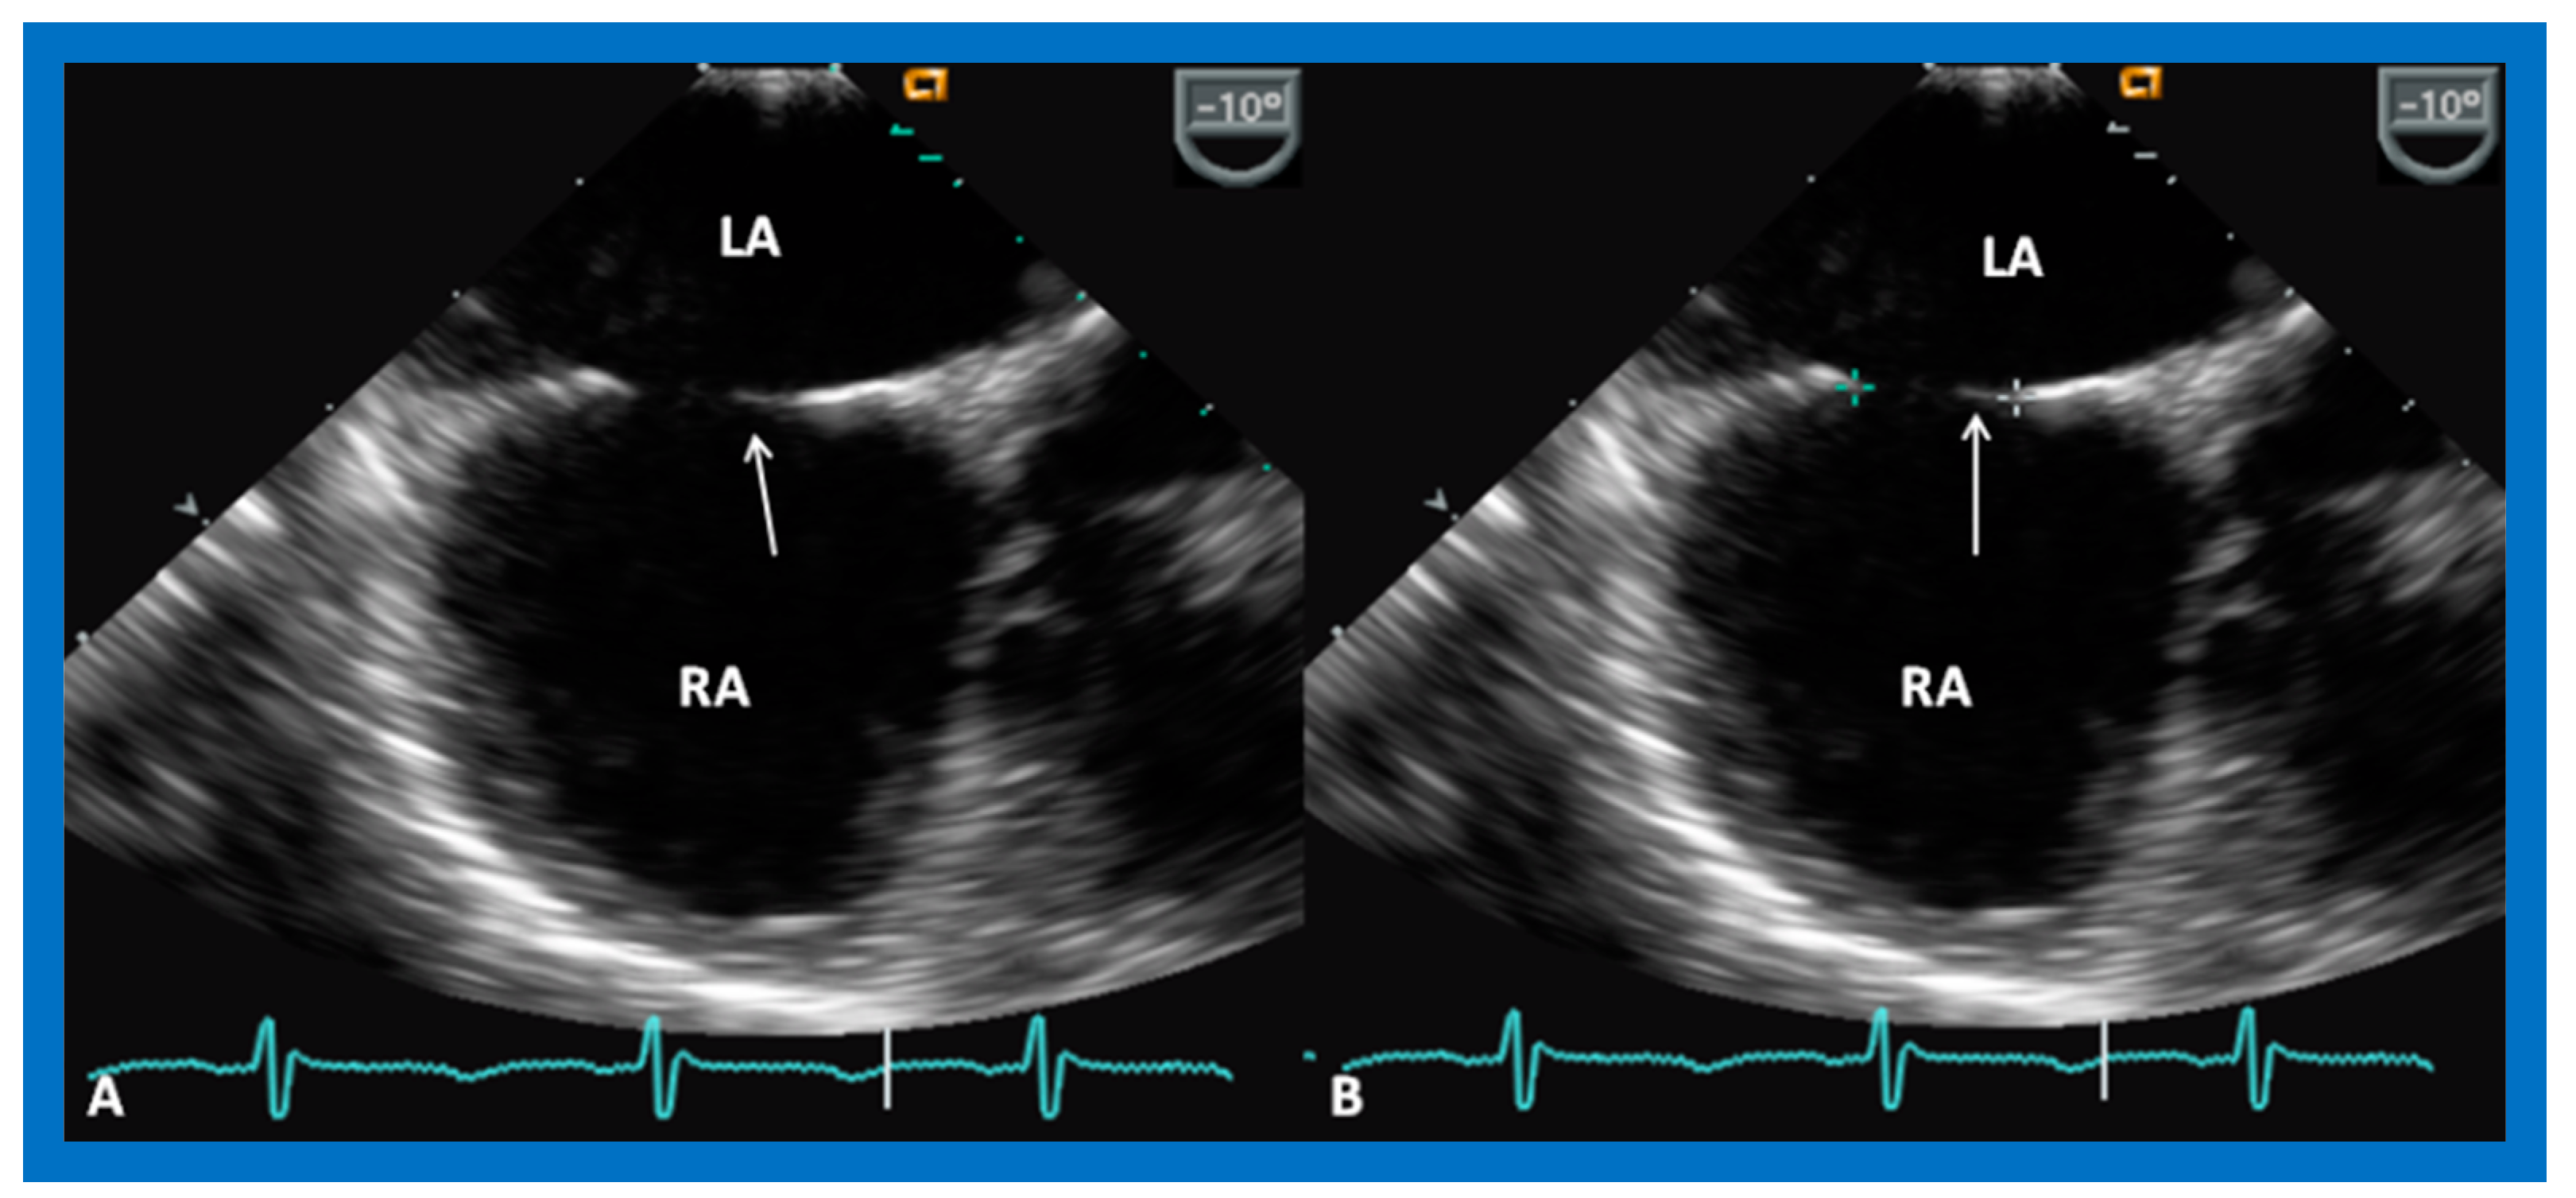

9.2. Device Position

9.8. Device Migration